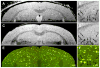

One of the cardinal pathologic features of Alzheimer's disease (AD) is the formation of senile, or amyloid, plaques. Transgenic mice have been developed that express one or more of the genes responsible for familial AD in humans. Doubly transgenic mice develop "human-like" plaques, providing a mechanism to study amyloid plaque biology in a controlled manner. Imaging of labeled plaques has been accomplished with other modalities, but only MRI has sufficient spatial and contrast resolution to visualize individual plaques noninvasively. Methods to optimize visualization of plaques in vivo in transgenic mice at 9.4 T using a spin echo sequence based on adiabatic pulses are described. Preliminary results indicate that a spin echo acquisition more accurately reflects plaque size, while a T2* weighted gradient echo sequence reflects plaque iron content, not plaque size. In vivo MRI-ex vivo MRI-in vitro histologic correlations are provided. Histologically verified plaques as small as 50 microm in diameter were visualized in living animals. To our knowledge this work represents the first demonstration of noninvasive in vivo visualization of individual AD plaques without the use of a contrast agent.